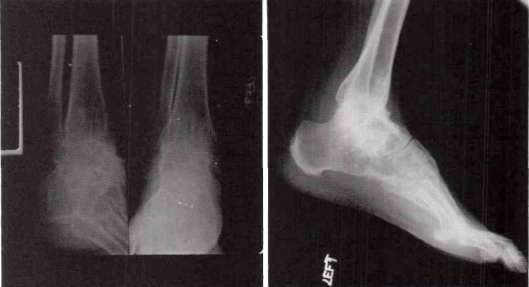

He was fitted with a PTB brace on March 27, 1968, and thus had worn it for slightly more than two years. The device is of a standard Durham type with a 90 degrees ankle stop and with approximately 5 degrees of dorsiflexion. The sidebars were of aluminum with an anterior aluminum calf band. A low shoe was worn with a build-up on the opposite side because of a shortening of the right leg related to the pelvic and femoral fractures. The brace was of the bivalve type. Fig. 19 and Fig. 20 show the condition of the foot and distal tibia and fibula over the period from January to October 1969. The patient reported that without the brace he experienced discomfort at the fracture sites, but that with the device he was reasonably comfortable and could wear the brace all day. He claimed that he took about 30% of his weight on the brace. Again, it appeared that this brace is a highly acceptable aid to the mobility of the patient.

|